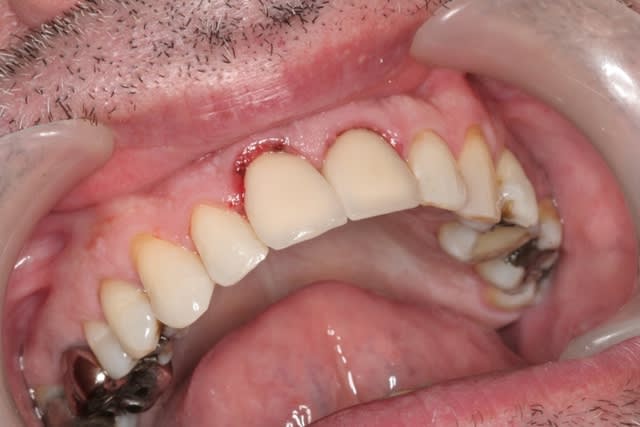

çà manque un peu de cas en ce moment...alors en voilà un ptit au passage...

11 avec résorption interne

EII avec MCI sur du dentium (4.5/14) comblement du gap vestibulaire avec du kasios tcp (très constant dans les résultats...et très économique)

pas de photos de chir par contre...j'ai du les effacer par erreur...grrrr...

la prothèse d'usage a été réalisée par ma petite associée...mais j'étais là pour superviser et faire quelques photos...;-)